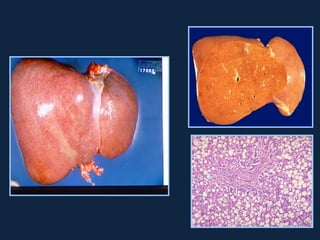

• Carcinoma

hepatocelular (HCC)

– TC:

T2

• Sem contraste: Hipo

• Intensificação arterial

– RM:

• T1: 

• T2:                      T1

• Diagnóstico # de nódulos:

– Nódulos de regeneração:

•   < 3 cm, T2: (Fe), intensificação portal

– Nódulos displásicos:

• > 3 cm, T2: (Fe), intensificação portal

– HCC:

• T2: 